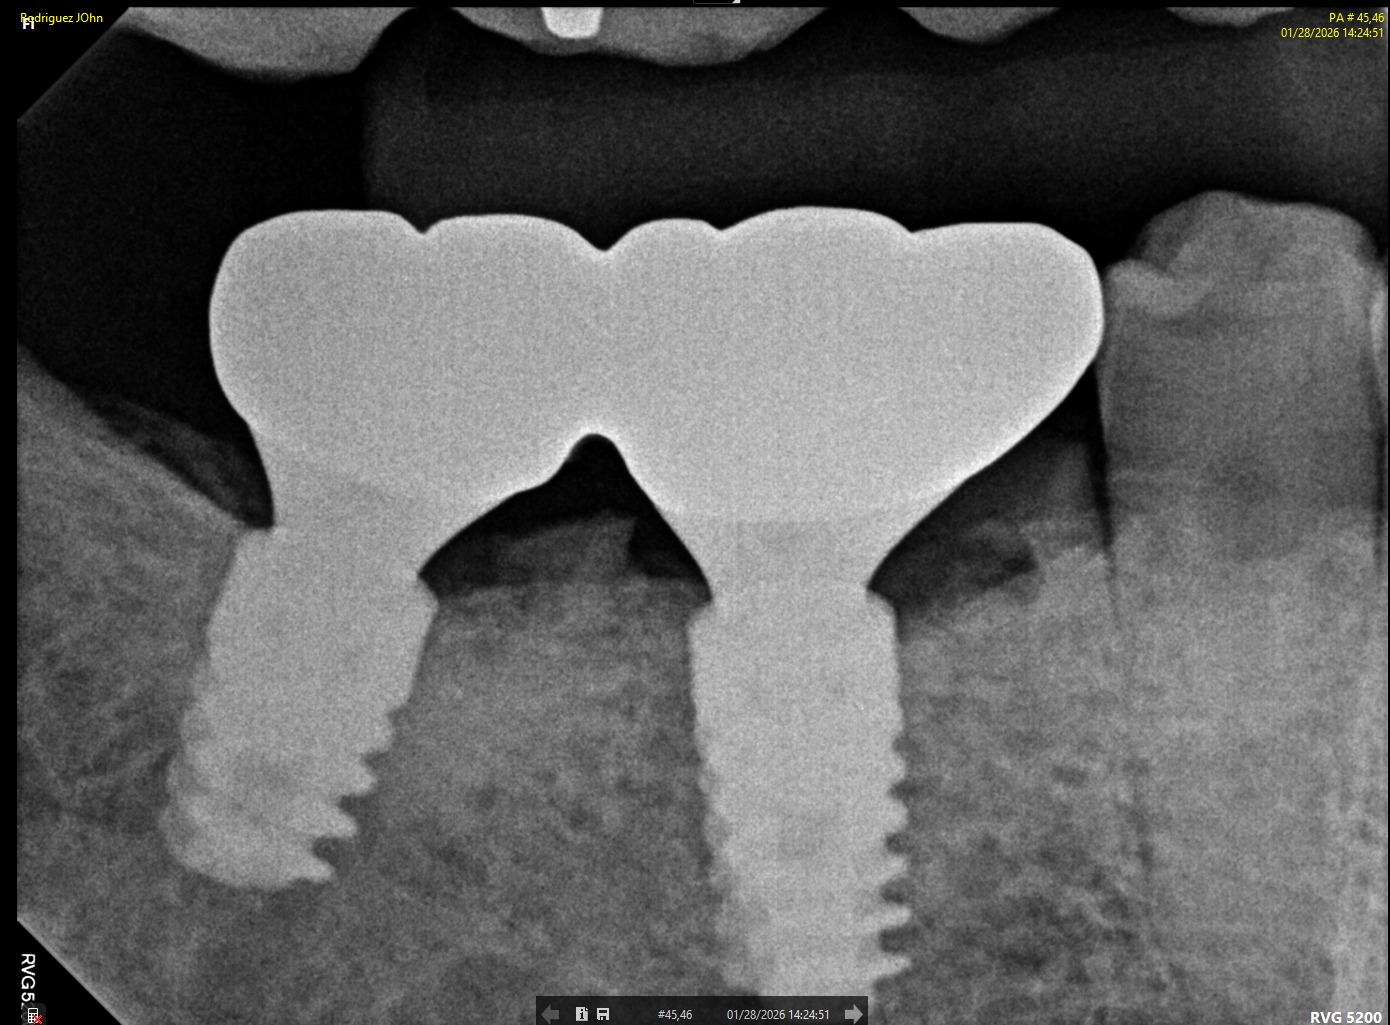

FOLLOW-UP - 2026

At the three-year follow-up:

• Peri-implant bone levels remained stable

• Soft tissues demonstrated healthy morphology and color

• The restorations maintained functional integrity under occlusal load

Both clinical and radiographic evaluations confirmed long-term hard and soft tissue stability, validating the treatment protocol and implant system used.